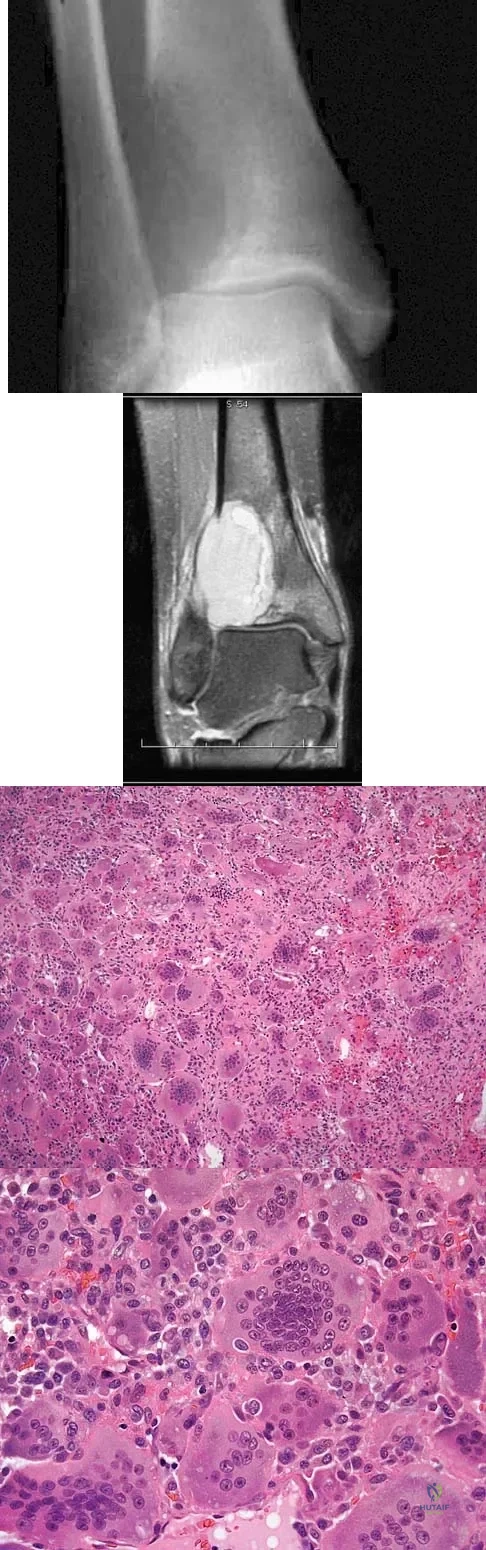

A 19-year-old girl has had pain and swelling in the right ankle for the past 4 months. She denies any history of trauma. Examination reveals a small soft-tissue mass over the anterior aspect of the ankle and slight pain with range of motion of the ankle joint. The examination is otherwise unremarkable. A radiograph and MRI scan are shown in Figures 45a and 45b, and biopsy specimens are shown in Figures 45c and 45d. What is the most likely diagnosis?

Explanation